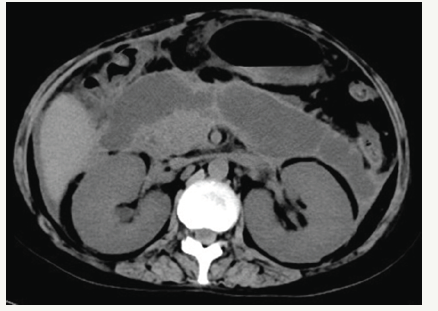

Figure 1:CT scan showing expansile pancreatic pseudocysts.

In June, she was admitted to our hospital because of persistent pyrexia. The laboratory data on admission showed that: white blood cell count (WBC) 16.11×10^9/L, C-reactive protein 67mg/L, which indicated the inflammatory reaction. Abdominal CT showed the presence of pancreatic pseudocysts and gall-bladder wall thickening (Figures 1 & 2), so percutaneous drainage was performanced. Yellow feculent liquid fluided from the drainage tubes. Thereby the bacterial, fungal culture and drug sensitivity experiments of the drainage were performanced. The result showed the presence of Enterococcus faecium, Pseudomonas aeruginosa, Enterobacter cloacae. Subsequently, fistulography via drainage tube showed the presence of a colonic fistula into the descending colon (Figure 3). Due to the unsatisfactory effect of conservative treatment, surgery was scheduled. The patient subsequently underwent transverse colostomy in August.